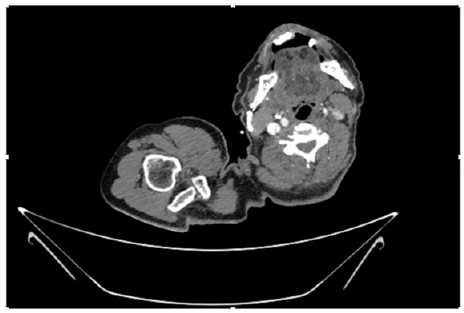

55-years-old chronic smoker had acute, severe pain in the right upper limb for one week; it was cold upto mid arm with skin discoloration. He also noticed numbness and weakness of movement of elbow joint. He underwent below elbow amputation in February 2023 for acute ischemia of left upper limb. He was a current chronic smoker; 15 pack year. General condition was weak; temperature was normal; blood pressure was 100/60mmHg; heart rate was 92/minutes with sinus rhythm; SpO2 was 97% on air; heart was normal. In lower extremities, all peripheral pulses were intact. Local Examination of right upper limb revealed as follows: tenderness; coldness; discoloration; decreased motor function and sensory modalities. Axillary, brachial and radial pulses were not palpable. Hand-held Doppler failed to detect any signal in arterial system; therefore, we arranged for emergency embolectomy. complete occlusion of right upper limb arterial system Full blood count showed high hemoglobin (14.6gm%); normal total WBC and platelet count. Coagulation profile was normal. Parenteral unfractionated heparin, antibiotics, tramadol, proton-pump inhibitors, anti-platelets and HMG CoA reductase inhibitors were given. Doppler ultrasound demonstrated complete occlusion of right upper limb arterial system. CT Angiogram illustrated occlusion of subclavian artery downwards on both sides. Figures 1-14 shows complete occlusion of right subclavian artery without collaterals. On Day ‘2’ of admission, the patient passed black tarry stool for 3 times. However, the vital signs were stable; blood pressure was 100/60mmHg; heart rate was 92/min; SpO2 was 97% on air; the abdomen was soft and not tender. Above elbow amputation was done on Day ‘2’ of admission. Intra-operative findings were as follows: (1) no active bleeding at brachial artery; (2) thrombosis along brachial artery; (3) muscle color and consistency were not healthy.

Figure 4: CT Angiogram at neck showing normal brachio-cephalic trunk, common carotid artery, and narrow right subclavian artery.

Figure 5: CT Angiogram at neck showing normal brachio-cephalic trunk, common carotid artery, and narrow right subclavian artery.

Figure 6: CT Angiogram at neck showing brachio-cephalic trunk, common carotid artery and narrow right subclavian artery.

Figure 7: CT Angiogram at neck showing brachio-cephalic trunk, common carotid artery and narrow right subclavian artery.

Figure 10: CT Angiogram at upper arm showing totally occluded right axillary artery; normal internal carotid artery and external carotid artery.